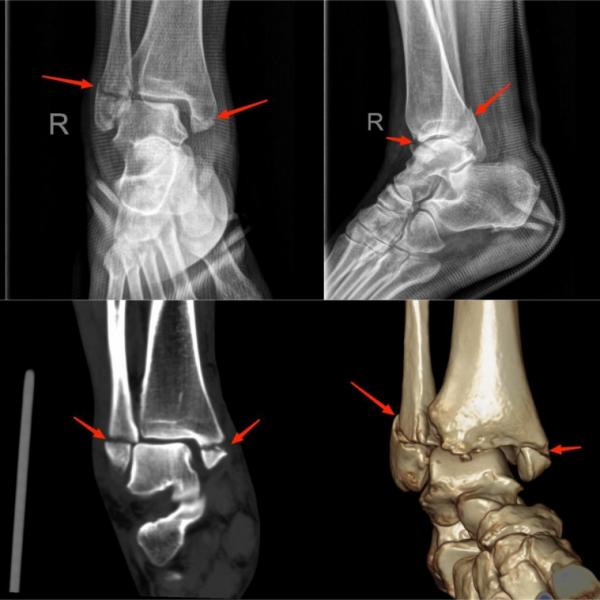

① 脚踝损伤

(上图为右踝关节内、外踝骨折)

常见原因:在运动过程中受力不当诱发,当足踝的关节超过正常的活动范围内,它周围的结构就会受到牵拉,从而会出现一些撕裂伤,如外踝撕脱骨折。